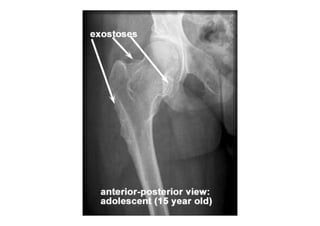

RADIOLOGIA DO

TRAUMA DO ESQUELETO

Referência: http://www.accessexcellence.org/RC/VL/